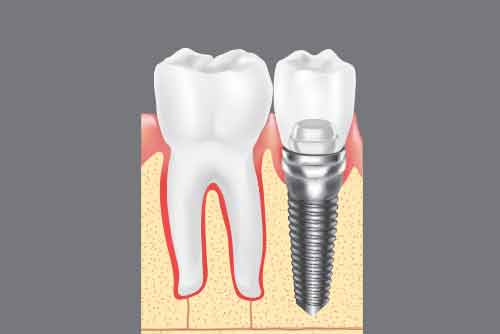

インプラントの構造

上部構造(かぶせの部分)

実際に表から見えるかぶせ物の部分です。材質は選べますが、生体にも優しいセラミックで作られることが多く、歯科医院でこの部分だけ外すことも可能なので、外して清掃を行ったり、修理したり、交換したり、ということが可能です。

アバットメント(接続部分)

上部構造とインプラントを固定するための接続部分です。

インプラント(人工歯根)

歯根に相当する部分で、顎の骨の中に埋め込まれます。ほとんどの場合、体に馴染むチタンでできています。埋め込む場所によって、様々なサイズがありますので、患者様に最適なものをお選びします。